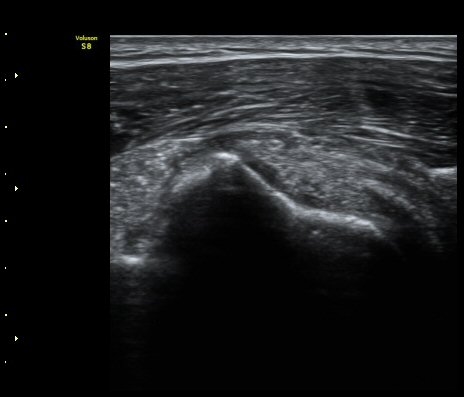

ÁÖ»ç ÈíÀΰú Á¡¾×³¶³» ÁÖ»çÄ¡·á(÷ºÎ ÆÄÀÏ) 1ÀÏ ÈÄ ½ÃÇàÇÑ °Ë»ç¿¡¼­ Á¡¾×³¶ÀÇ ºÎÁ¾ ¹× ¼®È¸ÀÇ

Á¦°Å°¡ °üÂû µÊ(±×¸² 6, 7).

ÃÊÀ½ÆÄ°Ë»ç¸¦ ÀÌ¿ëÇÑ Á¤È®ÇÑ Áø´Ü°ú ÀûÀýÇÑ Ä¡·á´Â Ç×»ó ÁÁÀº °á°ú¸¦ º¸ÀÓ.